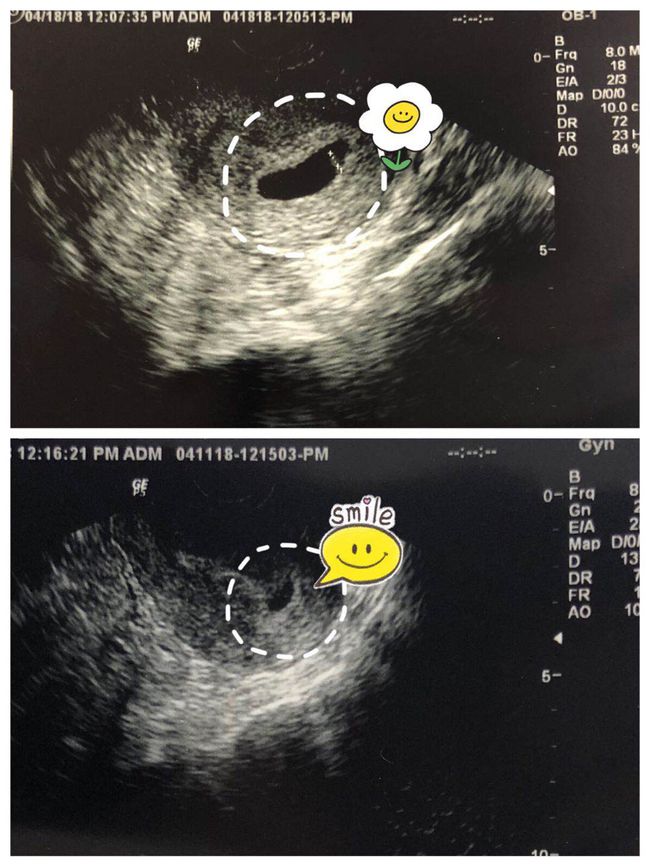

医生会使用超声波或排卵试纸等方法监测女性的排卵情况,以确定最佳的授精时间。